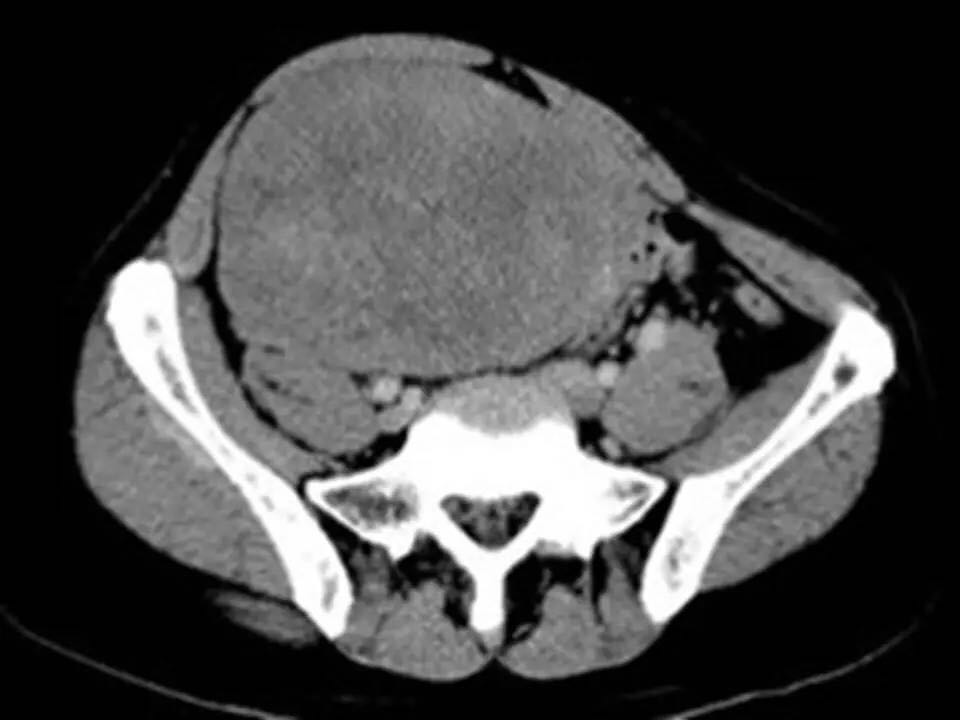

MRI表现,腹盆腔见不均质肿块,与肌肉相比为等低密度,强化不明显。T1WI信号均匀,T2WI高低混杂信号,增强后渐进性强化,病变各序列可见斑片状低信号区。 诊断,腹腔侵袭性纤维瘤病。

AF的影像学表现具有一定特征性。影像上表现为边界欠清的软组织肿块,钙化、出血少见,即便在较大的肿瘤中也看不到中央性坏死。病灶CT密度欠均匀,与邻近骨骼肌相近,强化不明显。T1WI信号基本均匀,明显或中度强化,典型强化方式呈渐进性。所有序列中都可以看到一定的低信号区,在病理上相对应的为病变内胶原纤维丰富的区域,此区域强化较轻。 侵袭性纤维瘤病虽然少见,但是平常工作中需要考虑到侵袭性纤维瘤病的诊断,尤其是中年女性腹腔的肿块。MRI为最佳的检查方法,可以显示一定的影像学特征。